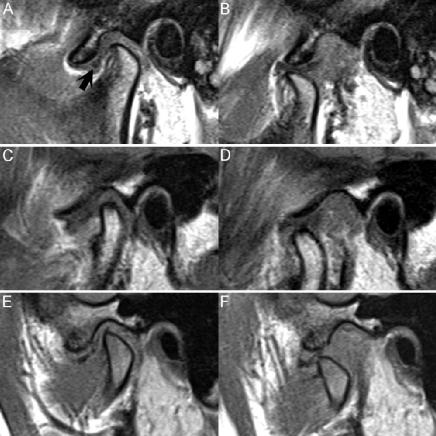

▲ 图90.1

图90.1的(A)闭口和(B)张口的FSE T1WI显示TMJ正常外观。下下颌髁突位于外耳道的前面,其头部与关节窝和颞骨的关节隆起相铰接。正常的双凹关节盘在T1和T2WI上均呈低信号。当(A)闭口位时,下颌髁突位于关节盂窝的中心,关节盘(黑色箭头)在其前上方。随着(B)张口,髁突移位至前方,关节盘移动至1点或2点钟位置。关节盘的后部附着于盘后双层区,该区含有弹性组织和脂肪,因此相对关节盘呈高信号。在出现病理变化时,这种高信号往往会消失。双层区将关节盘连接到髁后的颞骨。翼外肌位于关节盘前方,分为上、下头。前者插入到半月板的前内侧,对该结构施加牵引,以允许髁突通过翼外肌的下部向前移位。TMJ功能障碍最常见的原因是关节盘的前部可复性脱位,见图90.1C的闭口FSE T1WI。此处低信号关节盘位于下颌髁突前部,髁突位于盘后组织上。图90.1 D显示了这种脱位的可复性:髁突在关节盘后带下向前移位,使其在张口位显示为正常位置。如果没有这种复位,前部缺损被称为固定的或不可复性脱位。图90.1E,F显示了固定型脱位,在(E)闭口位图像中,关节盘再次出现在下颌髁突前方。在(F)张口位图像中,低信号关节盘仍然在髁突前方脱位。通常,固定的、慢性脱位的关节盘会因开合口腔过程中的重复性创伤而出现变形或压缩。当机械性阻塞阻止髁突向前移位时,就会发生所谓的髁突绞锁。如前所述,半月板的内侧或外侧移位通常在冠状图像上检测最佳。慢性情况下,可能出现关节盘穿孔,尽管关节造影术比MR更好地评估了这一点。也可能观察到关节软骨的粘液样变性,导致T2WI上信号增加。可能出现翼外退行性改变等间接表现,尤其是纤维化、萎缩和挛缩。肌肉中的脂肪信号置换导致T1WI上的信号增加。翼外肌下部筋膜增厚也可能是由于慢性关节盘前移位所致。慢性脱位的关节盘导致髁突与关节盘的后部附件而不是关节盘本身铰接,从而导致后部关节盘附件发炎和穿孔。可发生骨关节炎,表现为关节盂窝和下颌髁突沿线的骨赘和骨畸形。TMJ紊乱可能最终导致骨软骨炎或甚至下颌髁突的AVN(缺血坏死)。骨软骨炎表现为局灶性关节面下骨缺损,T1和T2WI上常为中央低信号伴高信号。TMJ内的骨关节炎变化与其他关节相似,包括髁突变平和关节窝畸形。伴随的软骨下硬化可在T1和T2WI上确定为低信号,而水肿样寻根表明关节内炎性变化。其他不太常见的关节炎包括TMJ病。尤其是炎性病因的检测,可通过获取CE T1WI得到帮助,其中在低信号关节液背景下,发炎滑膜将增强。